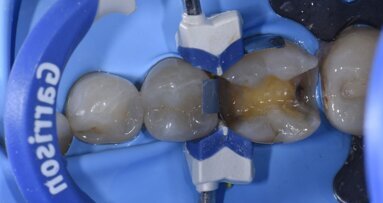

Viene posizionata una matrice Fusion FX175 e inserito un cuneo Fusion FXOR da vestibolare, per favorire la chiusura della matrice nell’angolo tra gradino cervicale e parete assio-pulpare vestibolare, resa difficile dalla rotazione dell’elemento 1.5 (Fig. 6). Si posiziona l’anello separatore FX400 - si noti il perfetto adattamento della matrice alle pareti assiali e al gradino cervicale. Quest’ultimo grazie soprattutto all’azione delle alette in silicone del cuneo (Fig. 7). Un’altra inquadratura evidenzia la profondità della cavità pulita (Fig. 8).